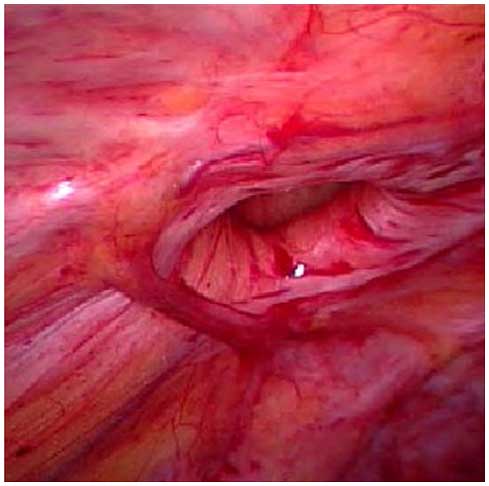

Gopi KrishnaLaser Stone Center offers the full spectrum of surgical treatments for incisional hernias, including minimally invasive procedures such as laparoscopic incisional hernia repair. For this procedure, surgeon carefully makes a few small incisions (10 mm & 5mm) for the laparoscope, which is a tiny camera that projects real-time images onto a television screen, allowing a surgeon to see inside the abdomen without major incisions. In addition to serving as ports for the laparoscopes, the small incisions serve as the portals for the medical instruments that a surgeon will use to cover the hernia with a small piece of mesh so that it does not recur.